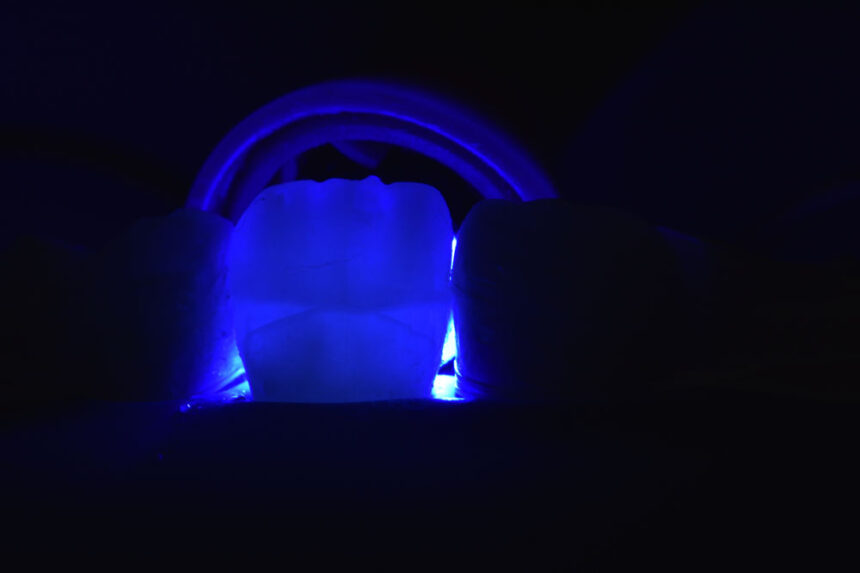

Στην εποχή της συγκολλούμενης αποκαταστατικής οδοντιατρικής ο έλεγχος της υγρασίας στο πεδίο εργασίας αποτελεί σημαντικό παράγοντα στην επιτυχία της τελικής θεραπείας. Ο οδοντίατρος καλείται να εκτελέσει σύγχρονα πρωτόκολλα διατηρώντας περισσότερη οδοντική ουσία και δημιουργώντας αποκαταστάσεις με μεγαλύτερη μακροβιότητα.

Στο σεμινάριο αυτό θα γίνει ανάλυση όλων των προτεινόμενων τεχνικών για την εφαρμογή της ελαστικής απομόνωσης σε άμεσες θεραπείες, σε συγκόλληση έμμεσων αποκαταστάσεων, σε συνθήκες επαναπροσδιορισμού του αυχενικού ορίου, στην εφαρμογή της σε περιστατικά ενδοδοντικών διαδικασιών., καθώς και στη χρήση αυτής σε ψηφιακή αποτύπωση. Αφού αναλυθεί ο κύριος εξοπλισμός και παρουσιαστούν οι αντίστοιχες προσεγγίσεις, ιδιαίτερη σημασία θα δοθεί στο πρακτικό μέρος της εξάσκησης των συμμετεχόντων σε σενάρια που προκύπτουν στην καθημερινή κλινική πράξη.